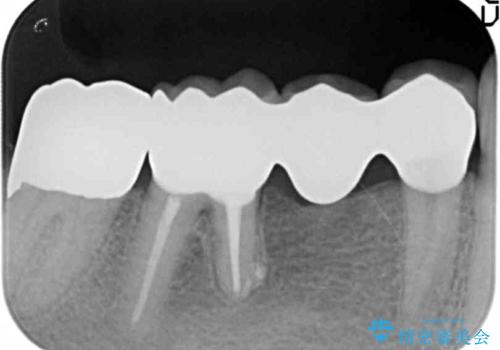

- 右下の奥歯がしみることを主訴に来院された患者様です。

精査したところ、横向きに生えた親知らずのせいで隣の歯(右下7)が虫歯になっていました。

親知らずを抜歯して隣の歯のう蝕を除去し、歯肉の治癒をしっかり待ったのち、患者様のご希望によりゴールド(PGA)クラウンによる補綴を行いました。

その後ブリッジの治療も希望され、オールセラミックのブリッジによる補綴を行いました。

右下7:ゴールド(PGA)クラウン

右下⑥5④ブリッジ:オールセラミッククラウン スタンダード